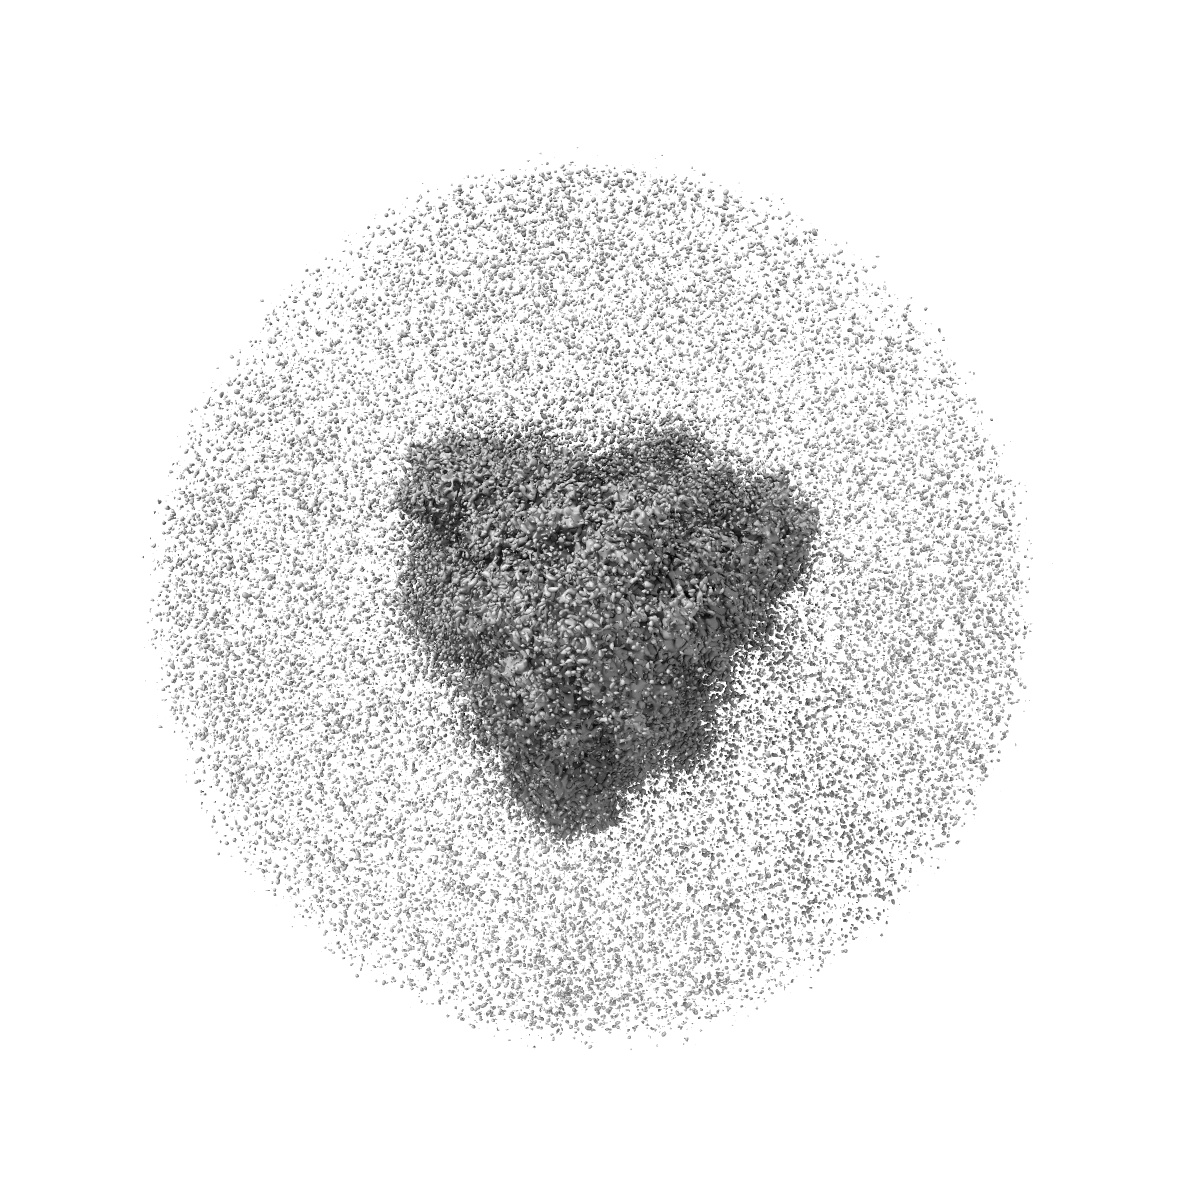

Cryo-EM Structure of SARS-CoV-2 BA.2 Spike protein in complex with BA7535

Single-particle2.44 Å

Sample: Cryo-EM structure of SARS-CoV-2 BA.2 Spike protein in complex with BA7535